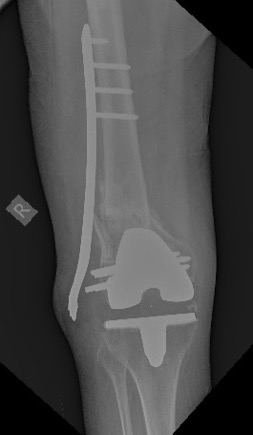

эКак оказалось в нашей ЦРБ сделали уже сегодня шеф решил без СТ. Пациент 41 года с большим количеством патологии. То есть полных 76 лет.

Норм остеосинтез но я в данном случае только за аппарат

Принципиальный момент- стабилен ли бедренный компонент? Если компонент изначально стабилен, что в данном случае мало вероятно), то все ок. Наилучшие результаты при использовании ИМ остеосинтеза (хотя могут быть проблемы с репозицией и размером гвоздя), затем блокированные пластины, затем все остальное ( последнее время много статей про применение аппаратов наружной фиксации). В данном случае длинна пластины корректная, но в зоне перелома слишком много металла, выше перелома должно быть 4-5 винтов, все бикортикально, с чередованием с пустыми отверстиями. То, что внизу торчат винты не очень good, но не так страшно. Консервативное лечение сопряжено с высоким риском летальности в течение первого года после травмы, вполне сравнимым с не оперированными шейками. Ключевой вопрос - стабильность бедренного компонента, теперь риторический).

А что правда кто-либо считает этот остеосинтез хорошим? По-моему беда! Шансов на сращение крайне мало, а для пожилого человека это может быть конец. Все принципы нарушены...

76 лет, остеопороз. В таких условиях требуется максимальное сохранение кровоснабжения в зоне перелома и фиксация с соблюдением принципа шинирования. Оно может быть накостным, интрамедуллярным или при помощи АНФ. В данном случае операция открытая, очень травматичная, куча винтов в зоне перелома, которые там неизвестно зачем, ну и серкляжи, которые могут стать последней каплей в убийстве кости. Из хорошего это действительно длина пластины, но при таком расположении винтов она (длина) не работает

Скорее всего, бедренный компонент не отклеился, так что это Rorabeck-Lewis II. Традиционный вариант - пластина с угловой стабильностью закрыто. Или две, чтобы от варусного коллапса подстраховаться. Мне больше бы импонировал антеградный закрытый интрамедуллярный остеосинтез.

1. Чаще всего у пациентов этого возраста перипротезный перелом после ЭПКС - последствие низкоэнергетический травмы на фоне выраженного остеопороза. Т.е. согласен с Михаил Панин, что следует поберечь кровоснабжение.

2. При определении тактики лечения таких пациентов, если оперативное лечение конечно возможно, ключевыми являются два фактора: стабильность бедренного компонента и размер дистального фрагмента. Если бедренный компонент нестабилен об остеосинтезе речи быть не может.

4. Принципы мостовидного остеосинтеза на показанных картинках не реализованы, в этом Панин безусловно прав.

Количество эндопротезирований растёт, поэтому с подобными случаями придётся сталкиваться чуть не каждому из нас. Или каждому. Думаю, следование принципам - абсолютная стабильность вокруг компонентов протеза и относительная - вне, не может вызывать особых дискуссий.

К сожалению (при этом желаю и хирургу, и пациенту удачи), выполненное вмешательство оставляет крайне мало шансов больному. Именно потому, что для метадиафизарной части перелома доктор пытался добиться абсолютной стабильности. Что не приемлемо при остеопорозе. Там и случится проблема, возможно, в самое ближайшее время. Я бы использовал остеосинтез пластиной - миниинвазивный для метадиафизарной зоны (как я понимаю, мы предполагаем, что ножка стабильна? ОК). Вот эти винты и завитушки на диафизе лишние и только демонстрируют не вполне гуманное отношение к биологии в этой зоне.

Учитывая, что протез без стабилизатора, межмыщелковое пространство абсолютно свободно и оптимальным вариантом в данном случае мог стать ретроградный интрамедуллярный остеосинтез с блокированием как самый малоинвазивный и сохраняющий и без того того повреждённое кровоснабжение через надкостницу. Выполненный накостный остеосинтез нельзя отнести к стабильному, к тому же по представленным рентгенограммам складывается впечатление, что винты проведённые через мыщелки обычные кортикальные, не фиксированы в пластине, серкляжные швы не придают стабильности. Потребуется длительная контролируемая реабилитация. Не исключается по результатам рентгенконтроля повторное оперативное вмешательство (костная пластика или всё-таки переход на интрамедулляный остеосинтез)